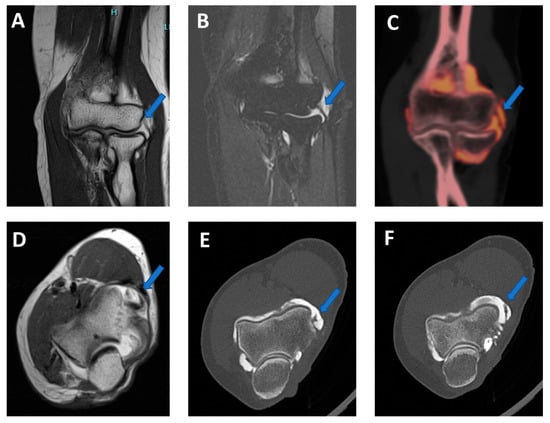

Figure 9.

Lateral plica syndrome at elbow arthrography. On the 3 mm coronal STIR and T1 weighted images (A,B), a tiny lateral plica (arrow) is depicted. The same plica is nicely depicted (arrow) on the corresponding reconstructed coronal 0.5 mm DECT iodine map image (C). On the 3 mm axial T1 weighted image (D), a partial volume effect does not allow for the correct image of the plica (arrow) and articular cartilages. On the corresponding 0.5 mm axial DECTA (E,F), the plica (arrow) and the adjacent articular cartilages are beautifully visualized without any artifact.